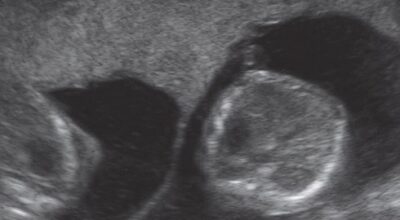

12/25

Ecografía de 3 meses: en la primera ecografía de un embarazo gemelar se puede precisar si existen una o dos placentas. En esta imagen, la presencia de la placenta en la barrera muestra un embarazo bicorial biamniótico, es decir, con dos placentas y dos sacos independientes.